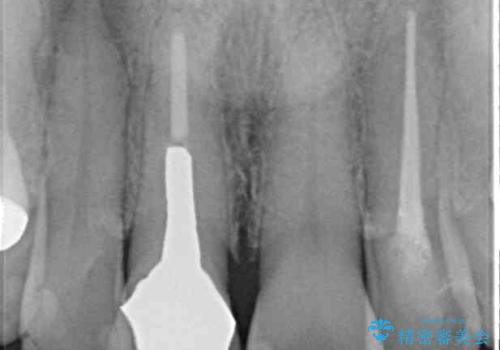

診断の結果、奥歯は歯根が破折しており、抜歯が必要な状況でした。

インプラントあるいはブリッジによる補綴治療が考えられましたが、前後の歯が大きな銀歯であったため、オールセラミックブリッジにより3本の歯を審美的に仕上げることとしました。

ところが、奥歯の治療を開始する前に、神経が失活して根尖部に病変のある前歯が著しく痛み出したため、根管治療を行うこととなりました。